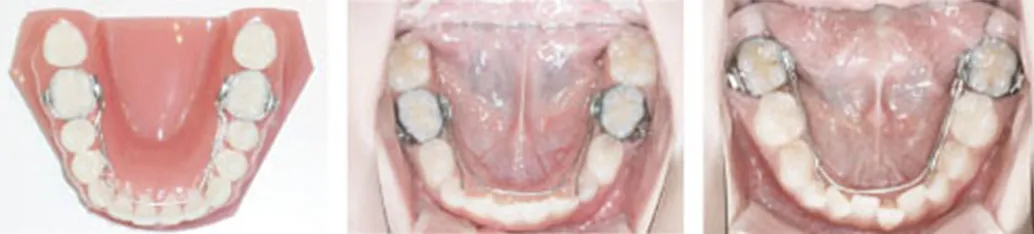

下顎の拡大装置

下顎の大臼歯にバンドと一体で装着し、歯列を拡大します。

緩徐拡大装置(バイヘリックス/Wアーチ)